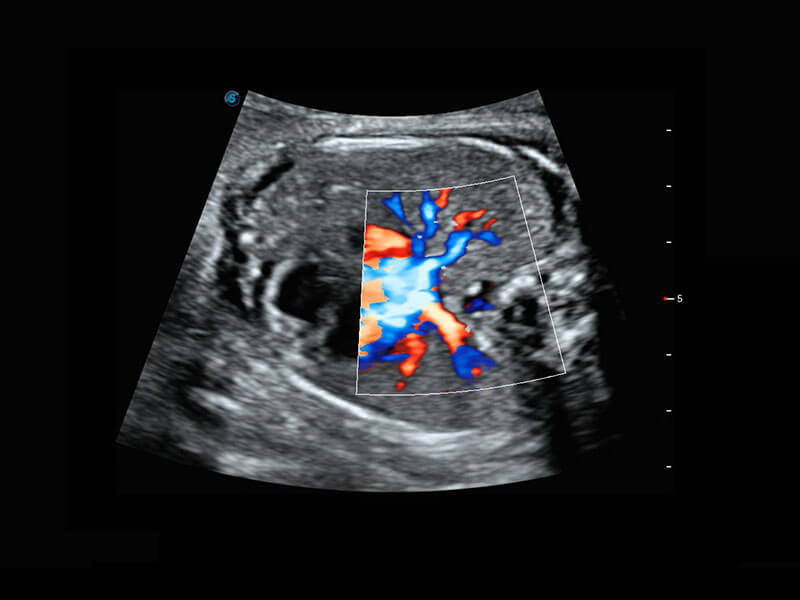

四腔切面

四腔心血流